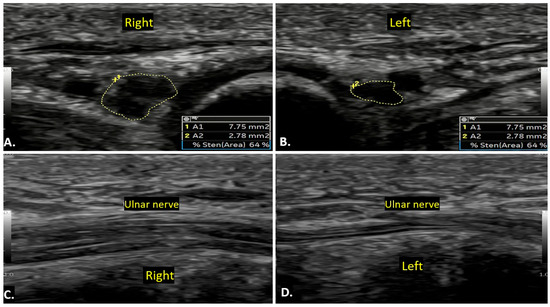

4.6. Idiopathic Ulnar Neuropathy

Compression of the ulnar nerve in Guyon’s canal is second to the cubital tunnel. Sometimes, the neuropathy occurs in the absence of any identifiable cause. This condition involves dysfunction of the ulnar nerve without a clear compressive cause, leading to sensory and motor deficits in the ulnar nerve distribution. On ultrasound imaging, the ulnar nerve may appear thickened with an increased cross-sectional area as compared to the contralateral normal side, with effacement of normal fascicular architecture in the affected segment (Figure 14). No compressive mass is generally seen. On MRI, the ulnar nerve may show increased signal intensity on T2-weighted images, indicating nerve oedema or inflammation.

Figure 14.

A case of idiopathic right ulnar neuropathy is illustrated. Image (A) shows an increased cross-sectional area of the right ulnar nerve compared to the left side (B), with a loss of the fascicular pattern. Image (C) presents a long-axis view of both wrists, highlighting the thickened right ulnar nerve in contrast to the normal left ulnar nerve (D). There is no evidence of a clear compressive cause.